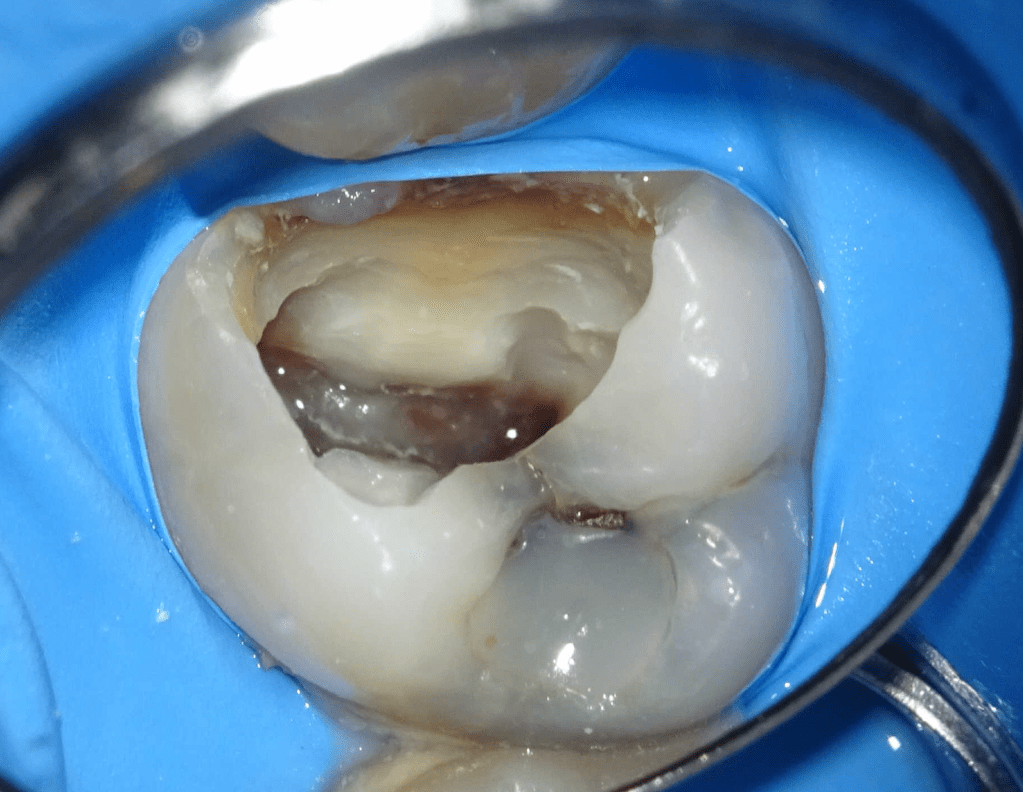

Fisura, remoción amalgama para explorar